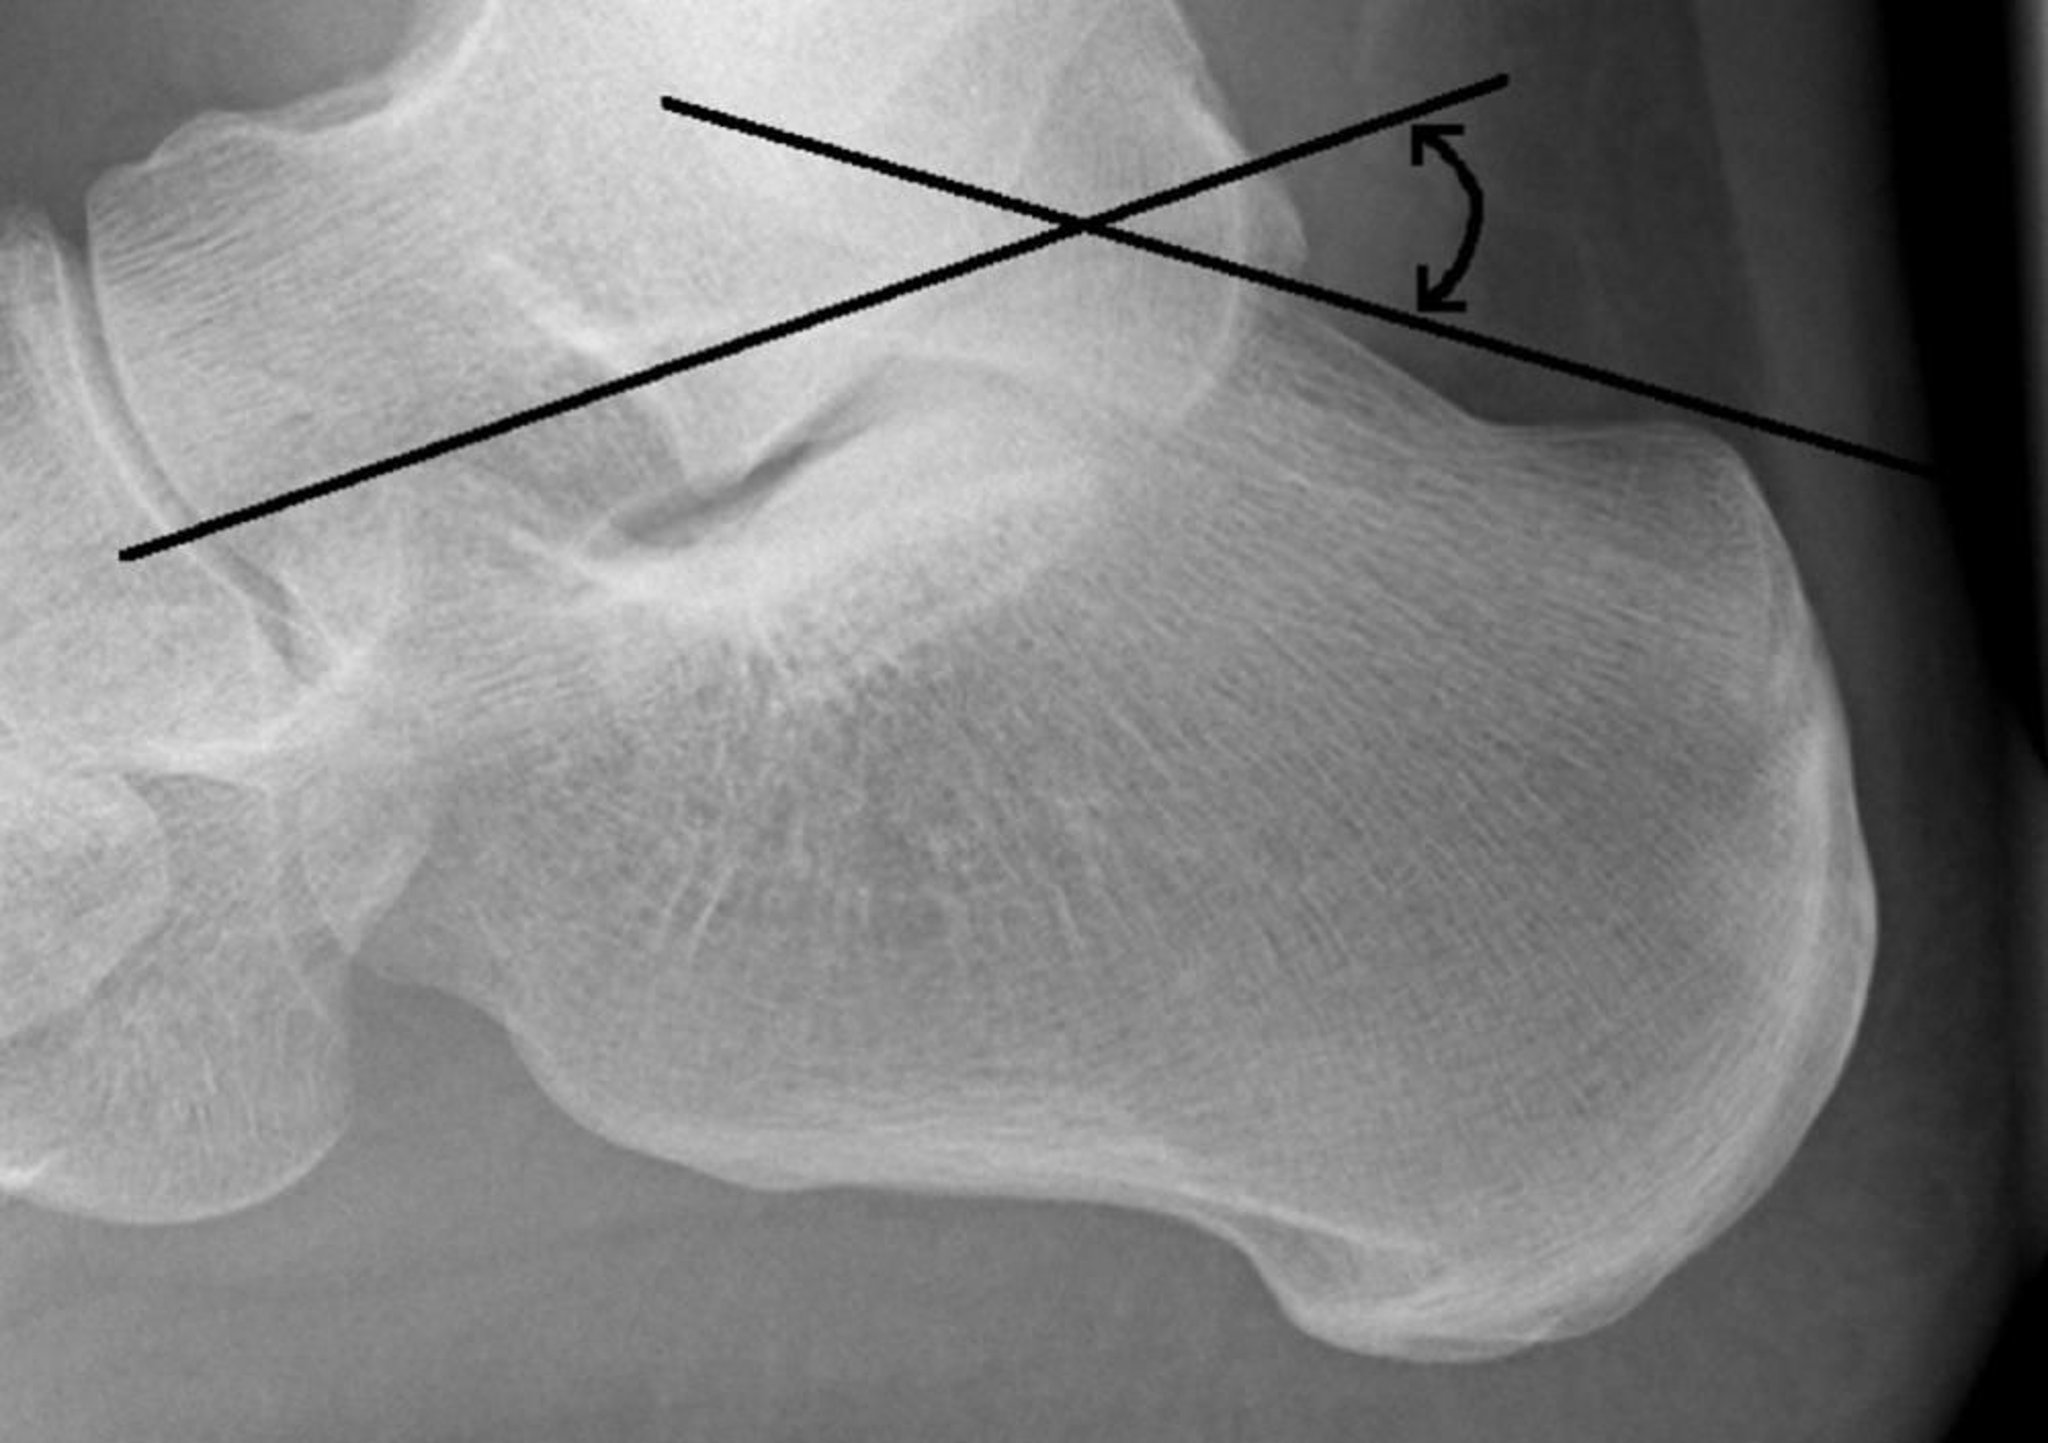

угол Белера

Угол Белера образован пересечением линии, проведенной от верхней части задней пяточной кости к верхней поверхности подтаранного сустава, и линии, проведенной от верхней поверхности подтаранного сустава к верхней части переднего отростка пяточной кости. В норме этот угол равен 20-40°. Угол < 20° предполагает перелом.

Image courtesy of Danielle Campagne, MD.